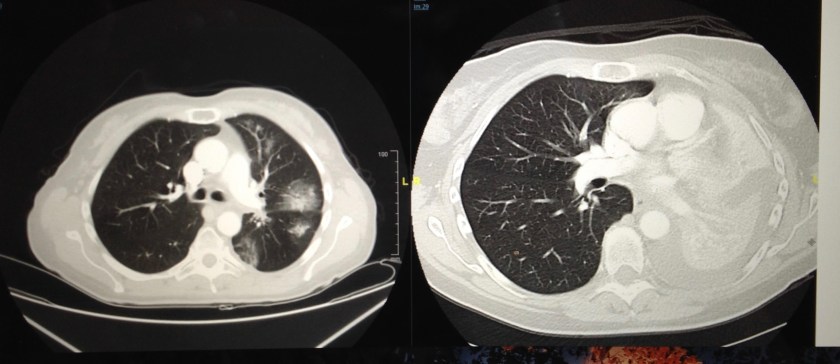

I know what it was like before my first targeted therapy drug. I was dying. I did not build resistance to it (but had brain progression). I am privileged to be treated in a facility where I have scans regularly, where I know when I have a symptom (such as with the brain progression) it will be looked into quickly, where treatments are known and available, where a plan is ready if cancer overpowers the drug. I know of an “other” , living in another country, who died while waiting for treatment to arrive. I am so sorry this happened.